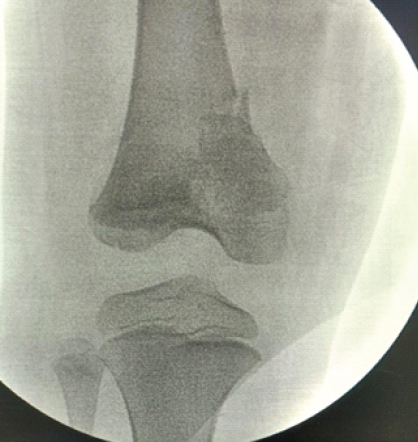

X-ray was advised, and findings were suggestive of a Salter–Harris type II fracture at the right distal femur (Fig. 2).

Figure 2: Pre-operative X-ray – anteroposterior and lateral views.